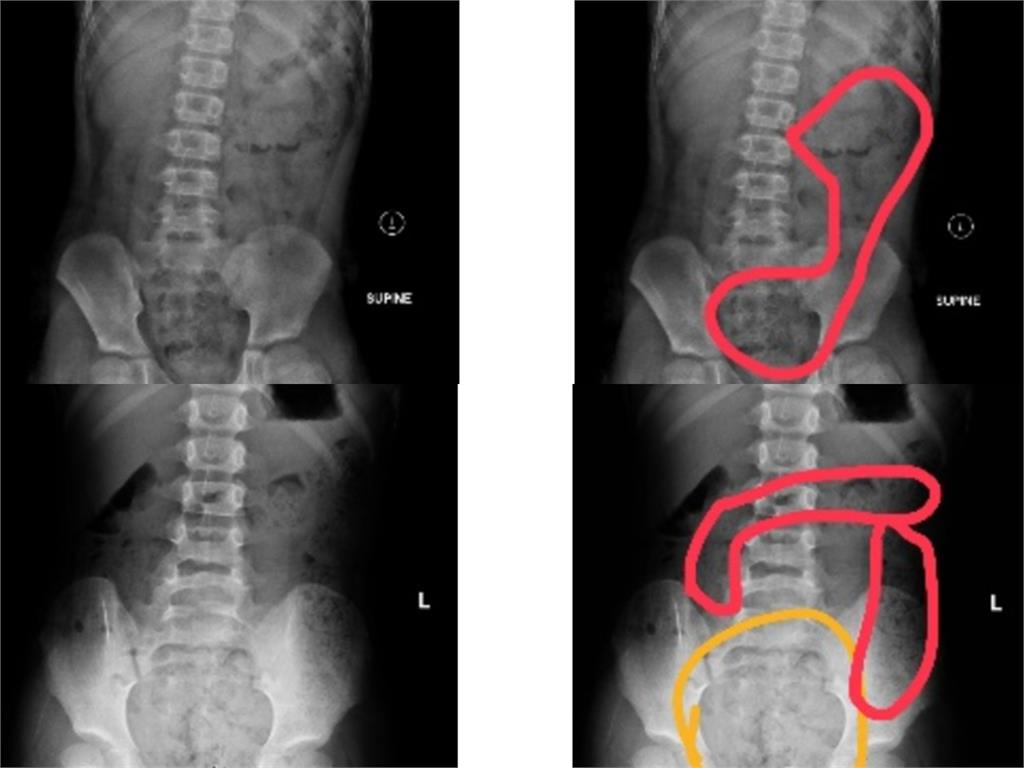

一名11歲小五男童因出現腹痛、冒冷汗、嘴唇發紫與手腳冰冷等症狀,被家人緊急送去急診,醫生診斷為嚴重便祕導致。然而,在灌腸後排出大量糞便,症狀隨即緩解。男童母親透露,自家小孩習慣邊上廁所邊滑手機,所以每次時間過長就會被催促,因此男童總是匆忙出廁所,自己也不知道有沒有上出來或上乾淨。收治病例的阮綜合醫院急診兒科主治醫師蕭宇超指出,近期有多例兒童便秘病例,一名6歲女童則因肚子痛而哭叫,加上腹部異常膨脹才被家長送醫治療,經過X光檢查後,發現腸道內有糞便堆積。女童母親透露,因女兒上小學後,還沒熟悉上課節奏,就算便意來了,也不敢說要上廁所,長時間累積導致情況越來越嚴重才掛急診。